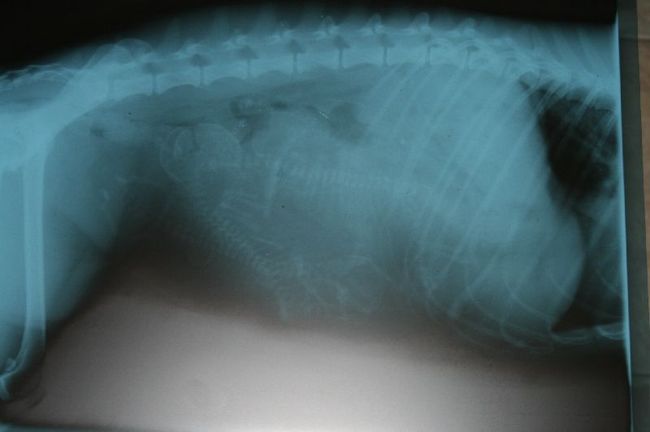

De fokker heeft de röntgen foto van vandaag gemaild.

Leuk om te zien. Ik zie 3 ruggengraatjes , maar de DA had er dus sowieso 4 gezien. Maar die 4e is voor mij verstopt

Haha, ik tel er ook 3. Maar zo'n foto is altijd zo moeilijk op de pc. Die moet je echt zien, om het goed te kunnen zien.

Hey iedereen ... is dit mooi of niet... het nieuwe leven! Prachtig! Ik denk er overigens ook maar 3 te zien.

Ik denk dat ik er 4 zie...

Je hebt er 2 linksonder 1 boven in het midden en volgens mij zit er ook nog 1 (van ruggengraat moeder naar onderkant buik moeder) achter de ribben van moeder verstopt, maar die is maar heel wazig te zien...

Het zijn er sowieso 4 (tenminste zei de DA en was ook op de eerste echo te zien)

Maar ik kan er maar 3 ontdekken.

Super die foto, maar eeehhh ik zie er zelfs 5

, soms is het een beetje vertekend, maar 4 zie ik er zowiezo........

@Janet, toevallig ik dacht er ook een 5de te zien maar heb gezwegen. Ik denk iets achter de andere 2 pups, linksboven..

Oftewel, linksonder, daar zie ik 2pups zitten en dat maakt het dan ook 5..

Oftewel, rechtsonder, daar zie ik 2pups zitten en dat maakt het dan ook 5..